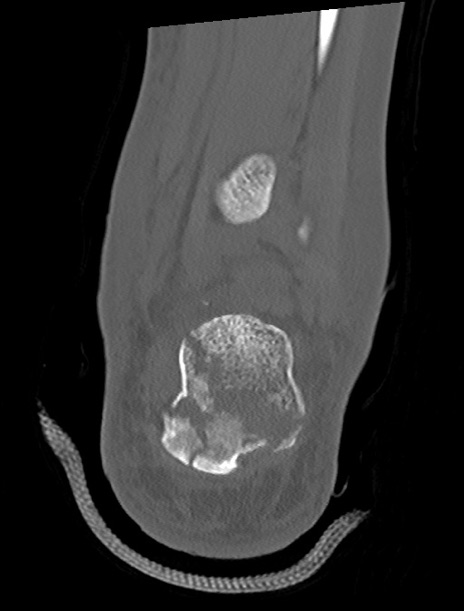

左足関節CT

横断像